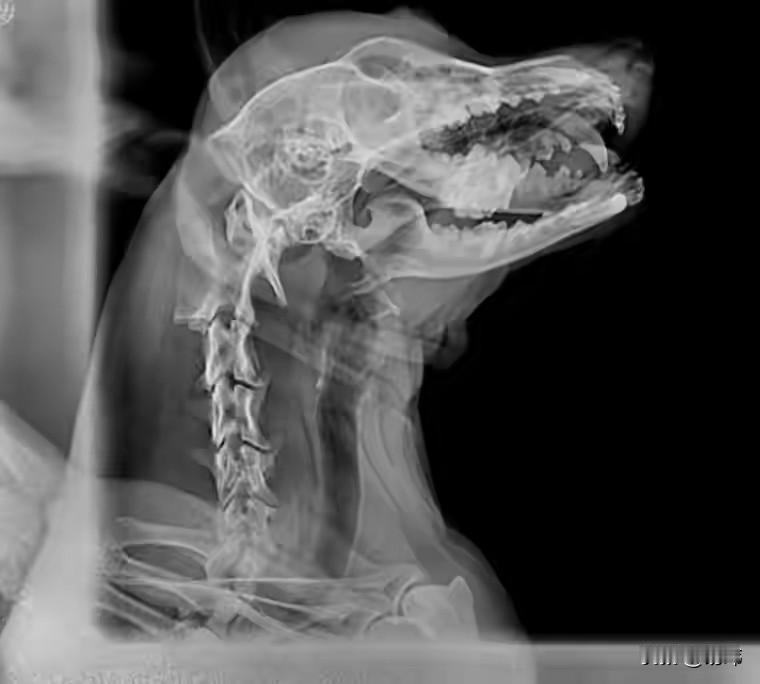

这天,一位大哥去河边钓鱼,结果在河边的沙地上看到无比凄惨的一幕,一只可怜的流浪狗被人打爆了头,一头都是血,善良的大哥顿时心生怜悯。 于是就决定救助收养这只可怜的狗狗,他先把狗狗送去宠物医院治疗,经过拍片发现它的头骨有骨折,需要手术并住院,后来在它出院后,大哥就收养了这只可怜的狗狗,相信在他的照顾下,这只狗狗也会越来越好的。